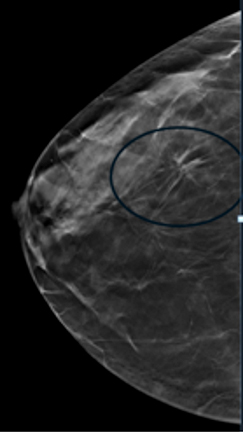

Compare these two images. You can see the benefits of 3D tomosynthesis. A small cancer (circled) on tomosynthesis slices in image A (left) is not apparent in the standard 2D mammogram, image B (right) of the same patient and same projection.

In 3D tomosynthesis, thin slices of the breast are obtained, and evaluation of the breasts is like flipping the pages of a book. This makes the examination more sensitive, improving the ability to detect invasive cancers by 15 to 22 percent, and reduces the likelihood of false positive and false negative results. (Breast Cancer Screening Using Tomosynthesis in Combination with Digital Mammography. JAMA 2014; 311 (24)2499-507. Sarah Friedewald et al).

Current scientific literature suggests that this is superior to the traditional 2D mammograms, which has some disadvantages.